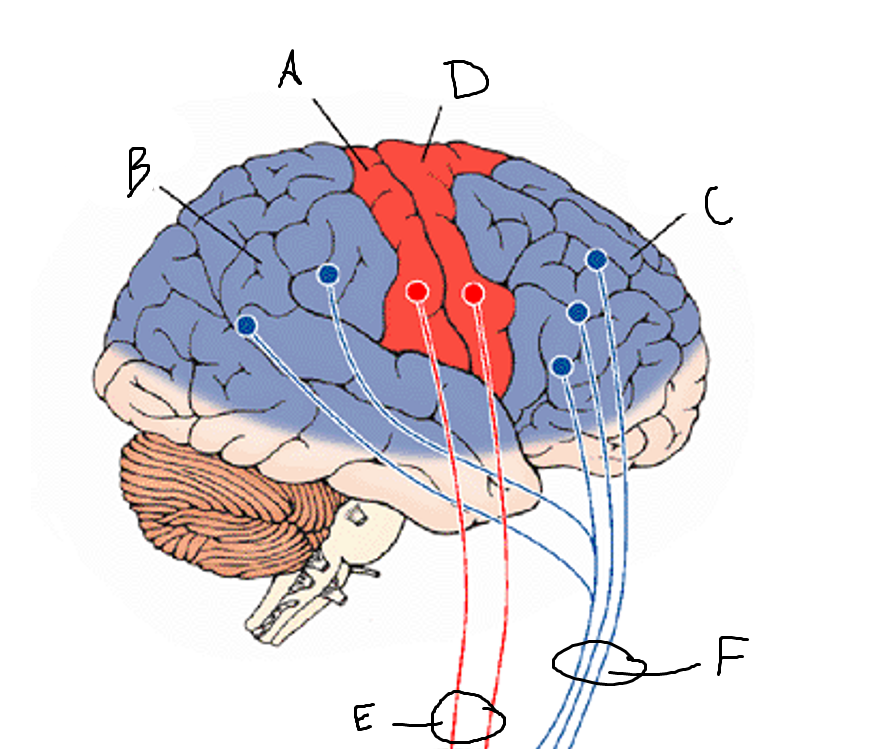

basal ganglia

A

somatosensory cortex

B

parietal association cortex

C

frontal and prefrontal cortices

D

primary motor cortex

E (where are the projections?)

putamen

F (where are the projections?)

caudate